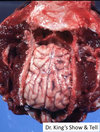

Tissue from a raven; what is the etiology?

Poxvirus